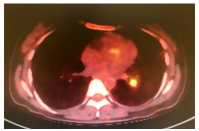

A 42-year-old female patient was admitted to the hospital with 38.6°C fever. Amoxicillin + clavulanate was prescribed due to a possible upper respiratory tract infection. Despite antibiotherapy, febrile period continued. Posteroanterior lung radiograph was performed which revealed no pathology, and the antibiotic was switched to clarithromycin. However, patient's fever persisted. When she applied to the infectious diseases outpatient clinic with 39°C of fever, acute phase reactants (APRs) were high (C-reactive protein: 56 mg/ dL). Urine culture was sterile, and there was no abnormality in lumbar puncture. Due to persistent non-productive cough, she was prescribed moxifloxacin 400 mg/day once daily. Although the patient used different antibiotics within the past three weeks, her fever continued and APRs were still high. Therefore, she was hospitalized. Aerobic/anaerobic blood cultures were sterile. Epstein-Barr virus, cytomegalovirus, and human immunodeficiency virus serologies were all negative. Abdominopelvic ultrasound was also negative for intra-abdominal abscess, hepatosplenomegaly, and pelvic pathologies. Transesophageal echocardiography revealed no abnormal findings. No tuberculous bacilli were detected by acid-resistant bacilli stain in the sputum and the urine. Gruber-Widal agglutination and Rose Bengal tests were negative. Carbapenem and antifungal drugs were added to the treatment in the second week of hospitalization. Despite these antibiotics and antifungals, her fever persisted up to 39°C. The patient had oral aphthous lesions for 10 to 12 times per year. During follow-up, thrombophlebitis developed in the vascular access in the left antecubital region. Intravenous catheter was revised, thrombophlebitis recurred on the right and confirmed by ultrasonography. After careful examination of perineum, there was a genital scar on the left labium majus. The patient was diagnosed with BS. As the fever is not a common problem in BS, PET-CT was performed to exclude possible malignancies. Moderately increased fluorodeoxyglucose (FDG) uptake (SUVmax: 1.14) was observed in the upper lobe posterior and lower lobe superior (Figure 1). Subsequently, methylprednisolone 40 mg/day was initiated. After five days of medium-dose steroid therapy, the patient’s APRs started to decrease, thrombophlebitis was cured, and her fever reached normal levels. Based on the PET-CT findings, the patient underwent pulmonary CT angiography and three aneurysmatic dilatations with a diameter of 11 mm were observed in the left main pulmonary artery (Figure 2). In the light of these findings, the patient was given methylprednisolone 1,000 mg for three days. Cyclophosphamide 1,000 mg/month was also planned with six cycles. After cyclophosphamide treatment, the patient received low-dose steroid and azathioprine 2 mg/kg/day and did not experience any fever attacks after approximately nine months of follow-up. No increase in the aneurysm size was detected in CT angiography at one year. A written informed consent was obtained from the patient for all diagnostic and therapeutic procedures.